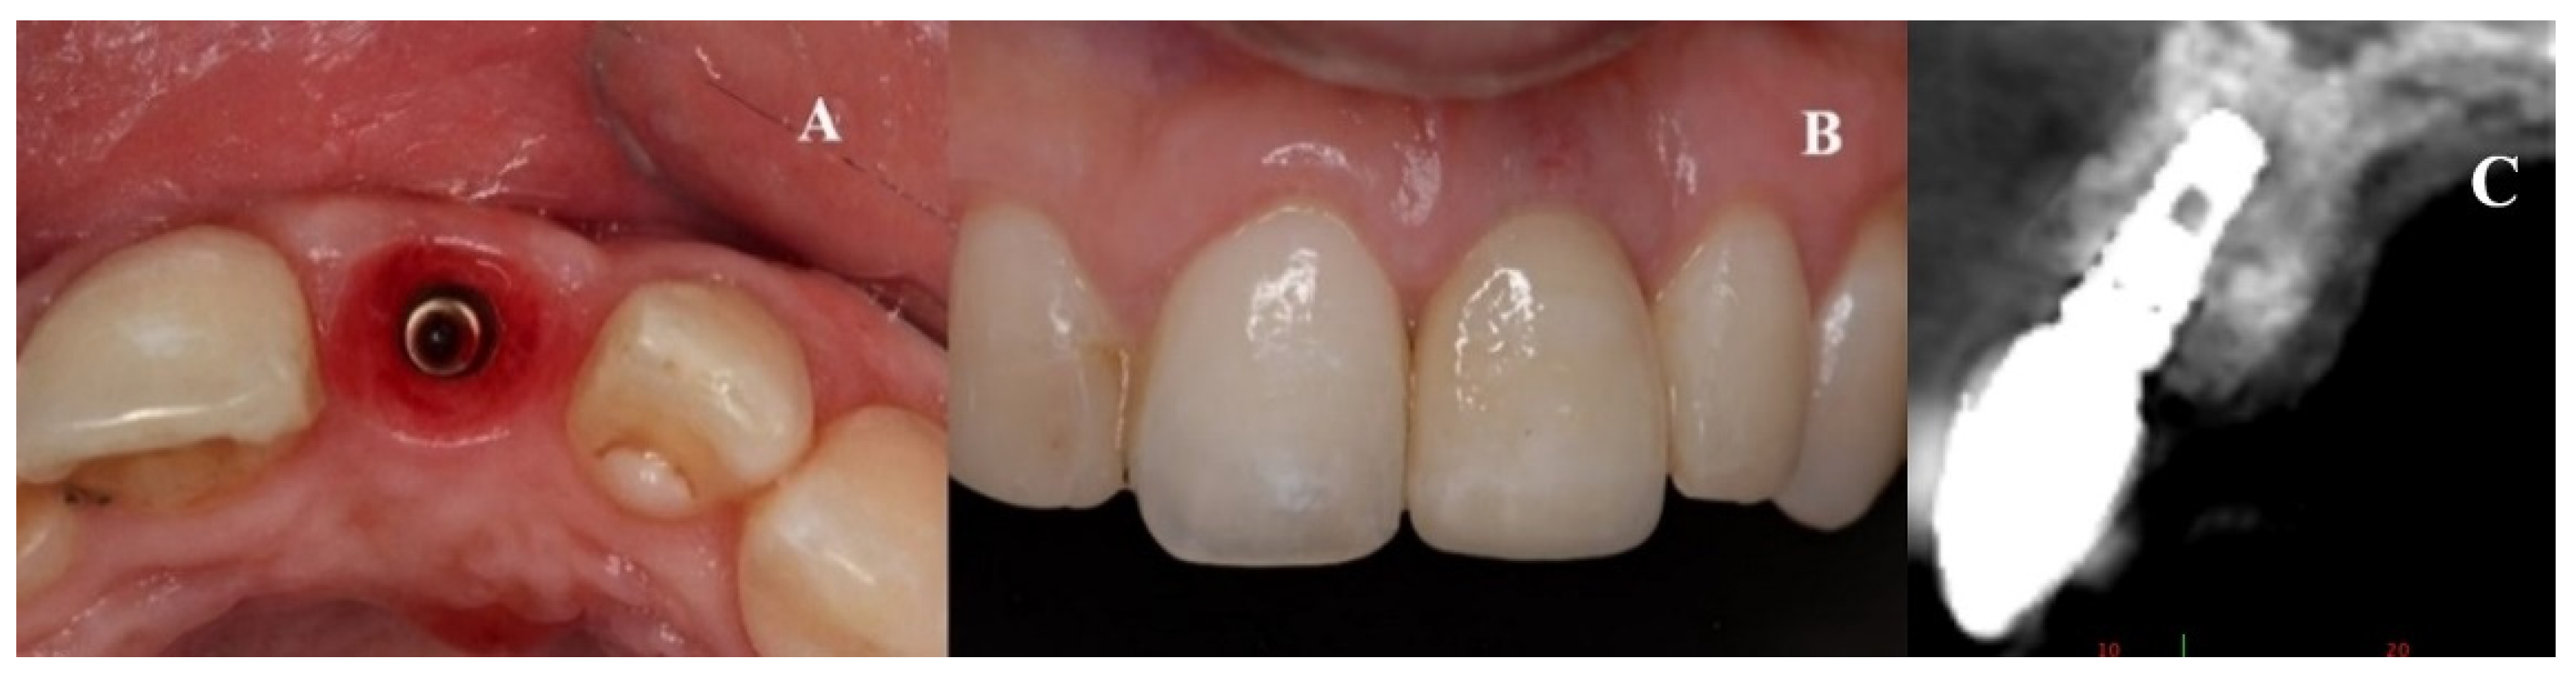

Figure 9.

(A–C) Placement of the porcelain crown.

Figure 10.

Radiographic control of Patient 1 at their 9-year follow-up. An occlusal view is shown on the left. (A) Sagittal view of the nasopalatine duct prior to treatment. (B) Post-treatment control radiograph: sagittal view of the implant in a three-dimensional position with the regenerated palatal wall.